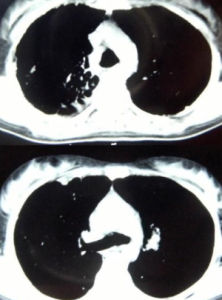

梅毒和HIV病人性接觸容易感染愛滋病,同時感染HIV(尤其是進展期的HIV)會影響梅毒螺鏇體感染的診斷\自然病史及治療,但是對於沒毒的治療原則在是否有HIV感染的情況下都是相同的。儘管有多個病例報導,但關於愛滋病合併梅毒的大型研究非常少。一些研究提示HIV感染可能會改變梅毒的臨床表現,使得梅毒的臨床損害更加厲害和加速梅毒性疾病的進展。合併HIV感染的早期梅毒同樣會引起一過性的CD4T細胞計數的減少和HIV病毒載量的提高。

一期梅毒同唱會表現為在接觸部位出現單個無痛性結節,然後迅速發生潰瘍形成一個典型的硬下疳;但是,在HIV感染的人群中,會出現多形態或者是不典型的硬下疳,原發性損害也許會缺失或者不明顯。

進展到二期梅毒需要2-8周的時間。即使在HIV感染的病人中由於嚴重的免疫缺陷會出現比較快的進展,但是其臨床表現和非HIV感染病人是相似的。

二期梅毒的急性梅毒性腦膜炎,可以類似於急性原發性HIV感染症狀;出現全身症狀以及不定位的中樞神經系統症狀和腦脊液異常。